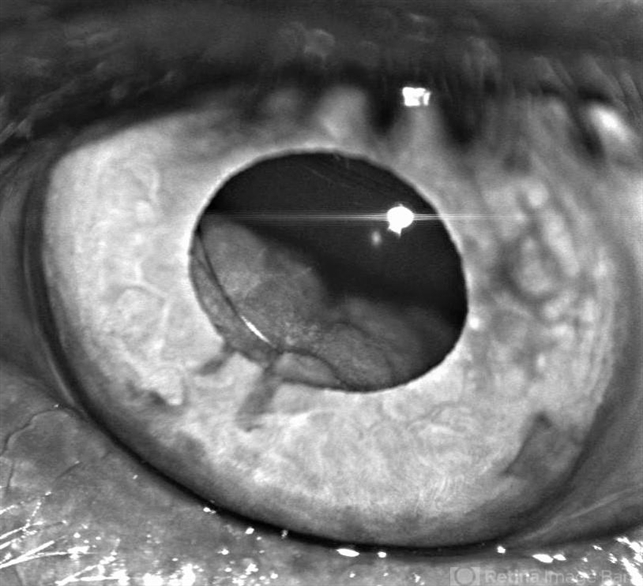

- ciliochoroidal melanoma, cataract surgery

- Belinda Rodriguez, Murray Ocular Oncology and Retina, Miami

- A 62-year-old male referred for a large ciliochoroidal melanoma OS noticed during cataract surgery. Visual acuity OS was 20/20.